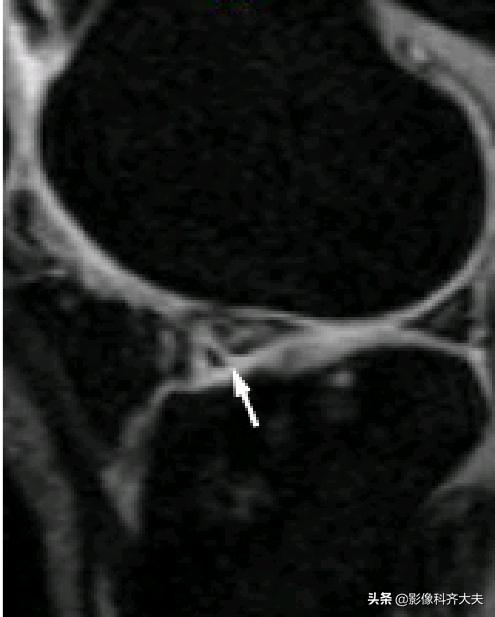

膝横韧带:

腘肌腱腱鞘:

后股板韧带:

关节内气体伪影:

内侧半月板后角上隐窝: